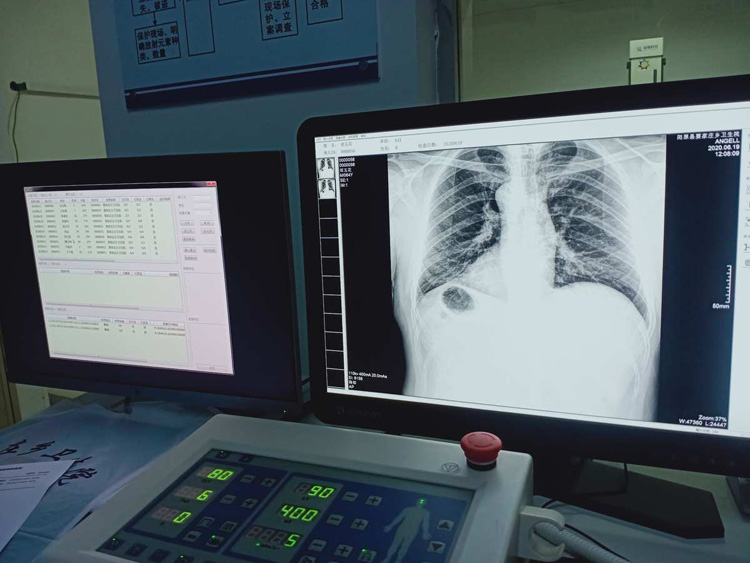

平床DR的平板探測器可以拍攝到高清的數字圖像。可以檢查身體的某個部位。頭部、胸部、腹部、上肢、下肢、正位、側位、都可以正常的拍攝。很小的劑量就可以采集到高清的檢查圖像。平板的穩定性也非常的強。DR的平板探測器跟圖像結合。噪音低、圖像的畫質呈現豐富。圖像的信息量會跟多提供給醫生參考。幫助醫生提高診斷的準確性。Digital Radiography就是數字化拍攝。平板探測器特性會對拍攝片的圖片質量有關係。

平床DR的數字影像高分辨率,動態範圍比較大,密度密度分辨率高可以看到更多細節。拍攝的速度快偽影小。比X光的的靈敏度高很多。輻射小的能量就可以拍到清晰的圖像。輻射量少30%以上。特別是對骨頭軟組織的效果更優。對結節的有沒病變的檢測查出率更高。